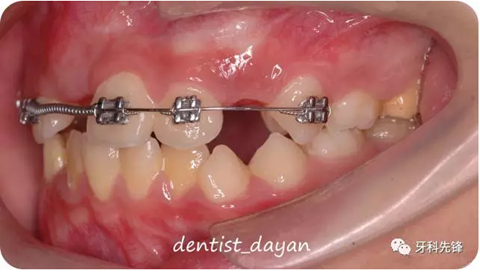

21推簧開辟間隙。。

4個月后,間隙開辟足夠,做翻瓣,暴露11,粘接舌側(cè)扣,初始用彈力線將11向he方牽引。

1個月后,待11可以粘接托槽時,粘接托槽,上鎳鈦絲將11繼續(xù)向HE方牽引。。